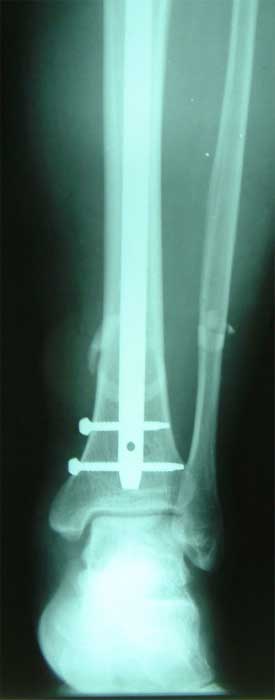

长骨干的力学特点是负重,两端为大关节,附着肌肉力量较大,应力突出。钢板内固定时广泛的软组织剥离,容易损伤血液循环和关节功能。 带锁髓内钉在骨组织和钉体之间提供较均匀的弹性应力分布,避免,抗旋转作用强于可屈髓内钉,不需外固定,对断端稳定性好,可早期功能锻炼。有优于钢板、外固定架和可屈髓钉的特点,已经成为治疗新鲜长骨干骨折的有效方法 。 但在长骨干骺端骨折、骨不连时,由于锁钉距离主钉孔较远,约在1.5-5.5厘米范围内,锁定骨折端有困难。 ZIMMER公司新型的带锁髓内钉可用于治疗长骨干骺端骨折、骨不连。由于锁钉距离主钉孔较近,约在0.5-3.5厘米范围内,可以满意锁定长骨干骺端骨折、骨不连。

胫骨中段、远端多段骨折,如果采用钢板固定,切口会很大,剥离骨膜,严重影响血运。由于中段、远端多段骨折,外固定架也难于获得满意固定效果。

采用特殊的带锁髓内钉固定多段骨折,可以采用闭合穿针方法,即不切开骨折部位的软组织,不破坏血液循环,不用外固定,可以早期锻炼关节,关节功能好,骨折愈合快。